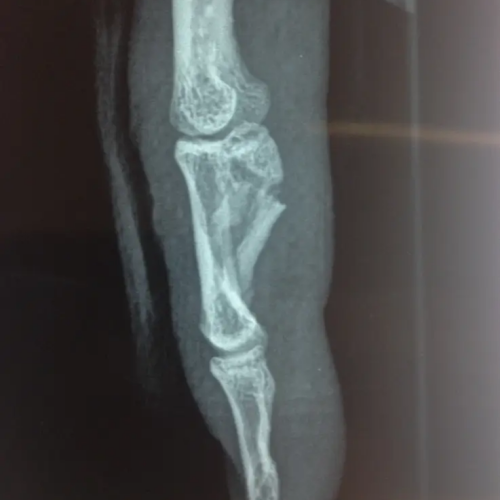

- fractures